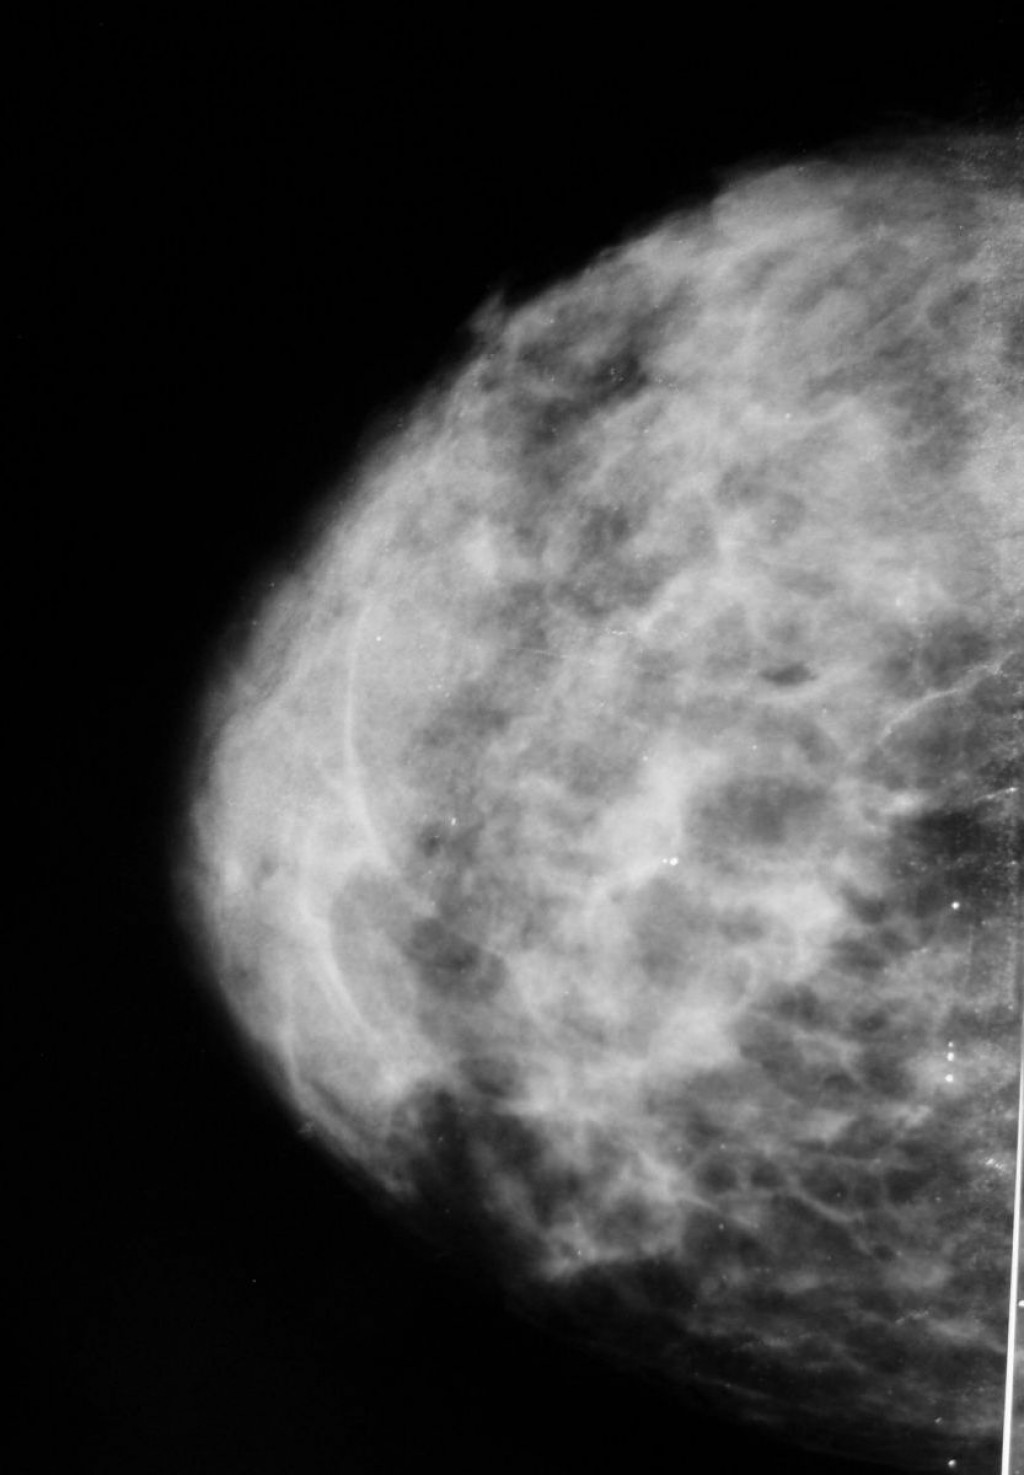

Плотность ткани молочной железы — это характеристика структуры груди, которая определяется соотношением железистых, соединительных и жировых тканей․ В медицинских понятиях она обычно сопоставляется с результатами маммографии, где ткани разделяются по степени плотности․

Классификация плотности груди по Бюро по раку молочной железы (BI-RADS) включает четыре категории:

- Категория A: практически полностью жирная ткань, низкая плотность․

- Категория B: разреженная железистая ткань, умеренная плотность․

- Категория C: смешанная ткань с заметным количеством железистых участков и соединительной ткани․

- Категория D: очень плотная ткань, преобладает железистая и соединительная компоненты․

Плотность груди важна потому, что она влияет на визуализацию на маммограмме и может быть связана с повышенным риском развития заболеваний․

Маммография, один из самых доступных и информативных методов диагностики заболеваний груди․ Однако эффект от этого метода напрямую зависит от плотности тканей․

Рассмотрим последствия высокой плотности:

- Затруднена диагностика: плотная ткань может скрывать мелкие опухоли, что снижает эффективность скрининга․

- Повышенный риск: женщины с высокой плотностью в 4-ой категории имеют в 4-6 раз больший риск развития рака груди по сравнению с низкоплотными женщинами․

- Необходимость дополнительных методов: при высокой плотности часто рекомендуются дополнительные исследования, такие как ультразвуковое исследование или МРТ․